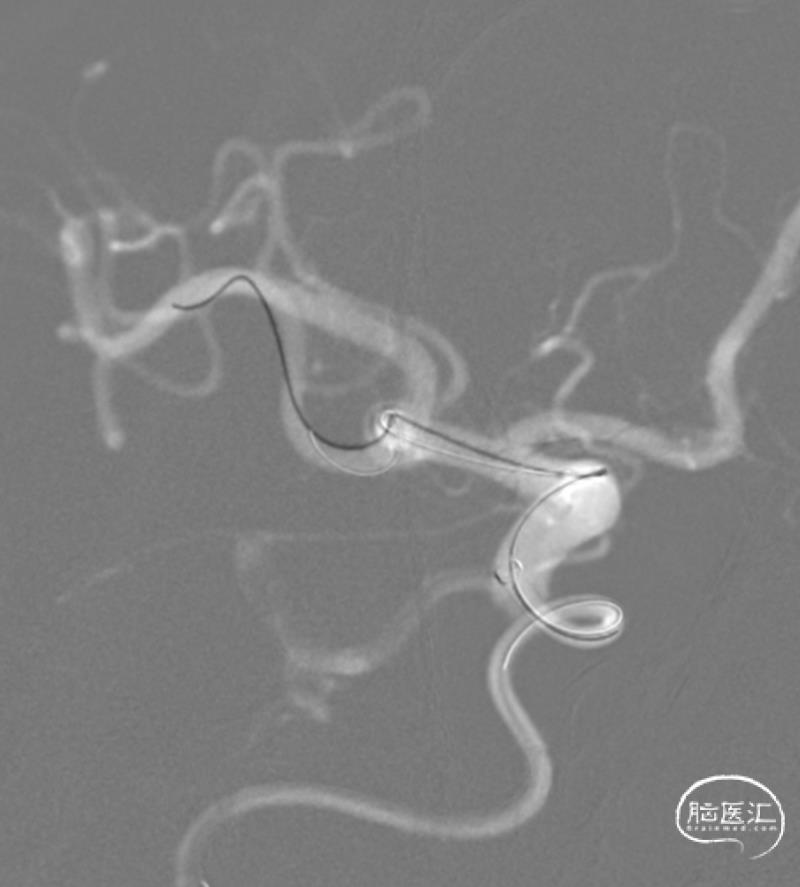

置入第2枚支架。

Neuroform Atlas 3mm×15mm,充分保护瘤颈。

支架到位。

支架释放。

结束前造影。

患者全麻复苏后出室,无神经功能缺损。一切顺利。